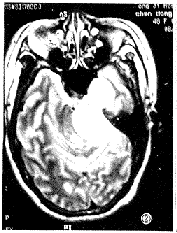

图1 左侧三叉神经鞘瘤。横轴位T1加权像显示肿瘤呈哑铃形,骑跨于中后颅窝之间,呈混杂稍低信号,中颅窝肿瘤边界清楚,可见肿瘤包膜,后颅窝肿瘤发生囊变,边界模糊,无肿瘤包膜。

图2 同图1病例,横轴位T2加权像显示肿瘤呈较均匀高信号,第四脑和脑干受压变形,同侧海绵窦受侵。